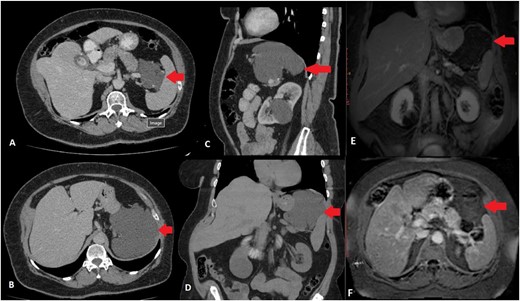

Upper abdominal US revealed cholelithiasis and a large well-defined cystic lesion in close relation with the upper pole of the spleen and the tail of the pancreas measuring 11.6 cm in diameter. Abdominal CT showed a hypodense, cystic lesion with minimal enhancement between the tail of the pancreas and the spleen (Fig. 1). The mass was well-defined, measured 12 cm anterioposterior (AP) × 9.5 cm transverse (TR) × 10 cm cephalocaudal (CC), without any signs of infiltration of adjacent structures. There were no calcifications or soft tissue component. Abdominal MRI confirmed microcholelithiasis without signs of cholecystitis and intra- and extrahepatic bile ducts within normal range. It revealed multiple microcystic formations in the body and tail of the pancreas with possible communication with the main pancreatic duct giving the impression of branch-duct intraductal papillary mucinous neoplasm. Furthermore, between the tail of the pancreas and the splenic hilum, expanding to the left hemi diaphragm, a large multilobulated cystic lesion was described. The size of the lesion was 12.8 cm (AP) × 10.2 cm (TR) × 8.65 (CC), originating from the tail of the pancreas and displacing the spleen laterally and caudally and the stomach anteriorly (Fig. 1). The cyst did not present any solid component and no pathological signal intensity. There were no evident pathological lymph nodes or vascular invasion from the mass. MRI findings were suggestive for atypical pseudocyst, mucinous cystic neoplasm, or cystic lymphangioma.

CT scan of the abdomen. Transverse scan—mass between pancreas and spleen (A), Transverse scan—mass expanding below the diaphragm (B), Sagittal scan—mass below the diaphragm and over the tail of the pancreas and splenic vessels (C), Coronal scan—mass between the diaphragm, upper pole of the spleen and tail of the pancreas (D), MRI scan of the abdomen. Coronal scan—mass between the diaphragm, upper pole of the spleen and tail of the pancreas, not enhancing (E), Transverse scan—mass between pylorus, pancreas, and spleen (F) ( arrow marking the mass).